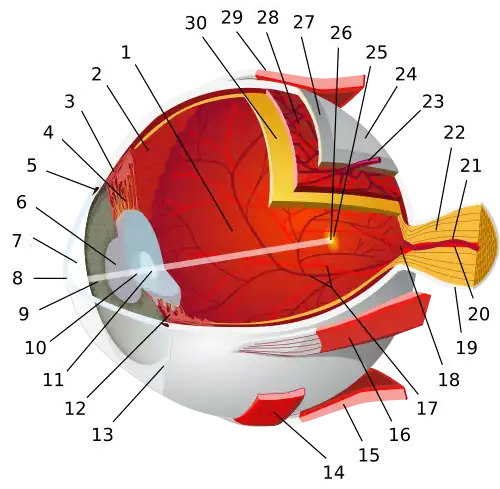

| Optic disc | |

Ophthalmoscopy photograph showing the optic disc as a bright area on the right where blood vessels converge. | |

The optic disc or optic nerve head is the point of exit for ganglion cell axons leaving the eye. Because there are no rods or cones overlying the optic disc, it corresponds to a small blind spot in each eye.

The ganglion cell axons form the optic nerve after they leave the eye. The optic disc represents the beginning of the optic nerve and is the point where the axons of retinal ganglion cells come together. The optic disc in a normal human eye carries 1–1.2 million afferent nerve fibers from the eye toward the brain. The optic disc is also the entry point for the major arteries that supply the retina with blood, and the exit point for the veins from the retina.[1]

Structure

The optic disc is located 3 to 4 mm to the nasal side of the fovea. It is a vertical oval, with average dimensions of 1.76mm horizontally by 1.92mm vertically.[2] There is a central depression, of variable size, called the optic cup. This depression can be a variety of shapes from a shallow indentation to a bean pot—this shape can be significant for diagnosis of some retinal diseases.